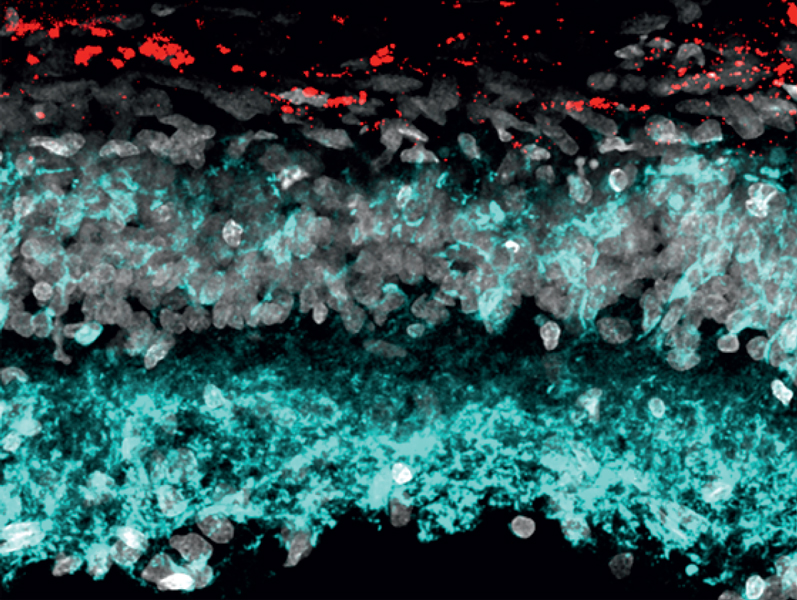

Light-induced charge generation in polymeric nanoparticles restores vision in advanced-stage retinitis pigmentosa rats |